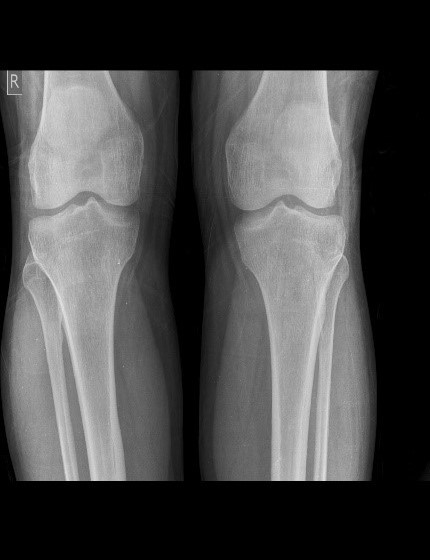

The dataset used in this research was collected by the Unani and Panchakarma Hospital, Srinagar, J&K, India [17]. It included X-ray images of the knee along with patient clinical data, covering variables such as gender, height (in meters), age, history of fractures, medical history, dialysis, joint pain, alcohol consumption, and site, which displayed identical values across different classes. Additional features, such as obesity, smoking habits, daily eating habits, diabetes, seizure disorders, family history of osteoporosis, and hypothyroidism, were also collected. However, these features were excluded as they were found to be uninformative based on feature importance analysis. Furthermore, variables with sparse data, such as the number of pregnancies and menopause age, were removed due to their limited availability across patients. Statistical details of the remaining key features, which were found to be most informative, are presented in Fig. 1. This study addresses a three-class classification problem, with the target categories being normal, osteopenia, and osteoporosis (2). Normal bone density reflects healthy bones with typical mineral levels. Osteopenia describes a condition where bone mineral density (BMD) is lower than normal but not yet low enough to be classified as osteoporosis. Osteoporosis represents a more severe reduction in BMD, resulting in brittle bones that are highly susceptible to fractures. Representative examples of X-ray images for each class are presented in Fig. 3. To streamline processing and ensure the model focused on the most relevant areas, regions of interest (ROI) were identified in the X-ray images. For patients with images of both knees, we randomly selected the left or right knee for analysis. The preprocessed X-ray images were then fed into pre-trained models for feature extraction.